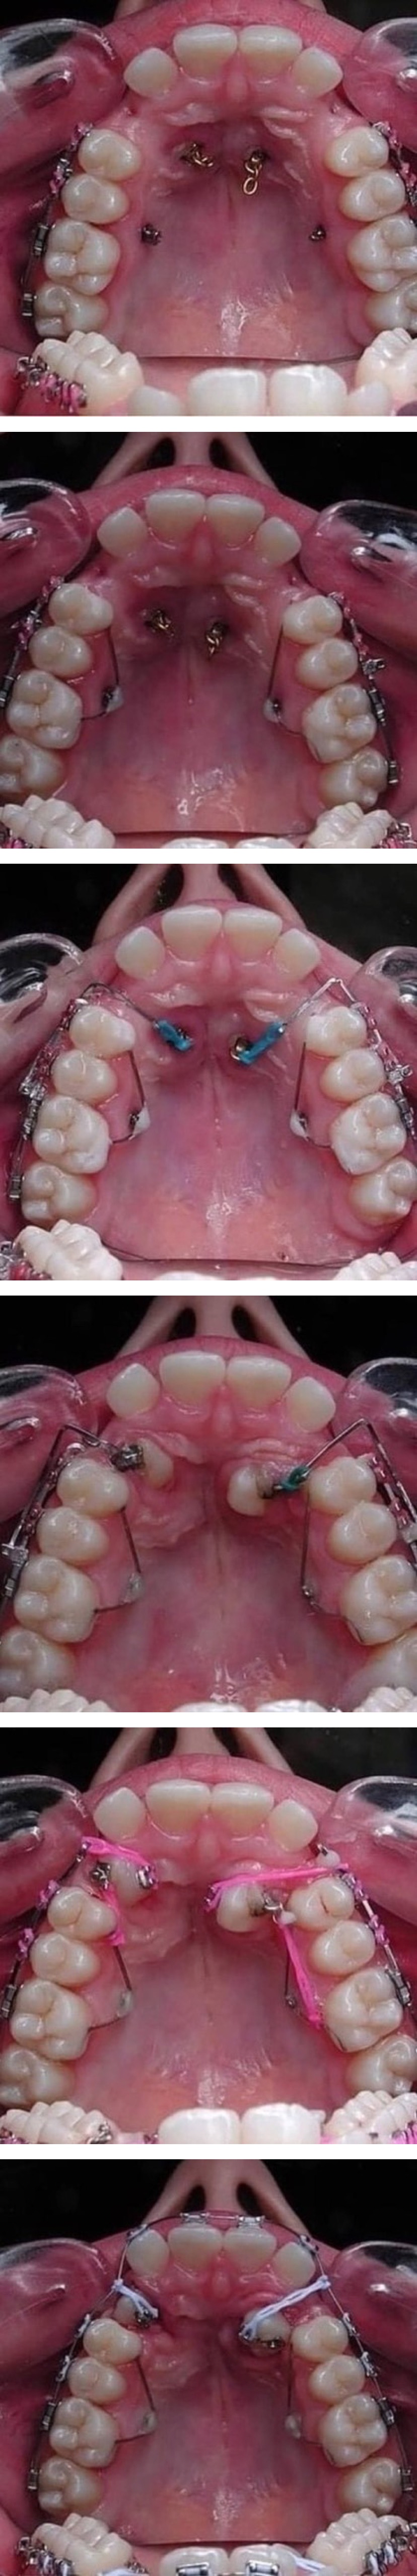

| Subject | [사람에 따라 약혐] 치아 교정 과정 |

천정에서 이 끌어 내리는거 정말 대단하네요 0